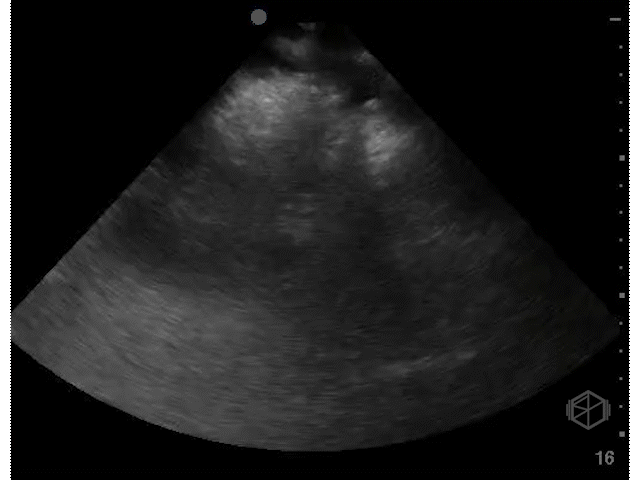

A 70's male with a history of nephrolithiasis presented to the ED with right flank pain worse over the last 4 days. Dr. Mendelow performed a POCUS immediately that showed:

Subsequent CT scanning later showed a 10 x 7 x 7mm right ureterovesical junction calculus within the urinary bladder causing moderate right hydroureteronephrosis, delayed nephrogram and mild perinephric fat stranding. The patient was taken to the OR for scope of bladder and right ureter; laser lithotripsy and removal of right ureteral stone and placement of right ureteral stent.